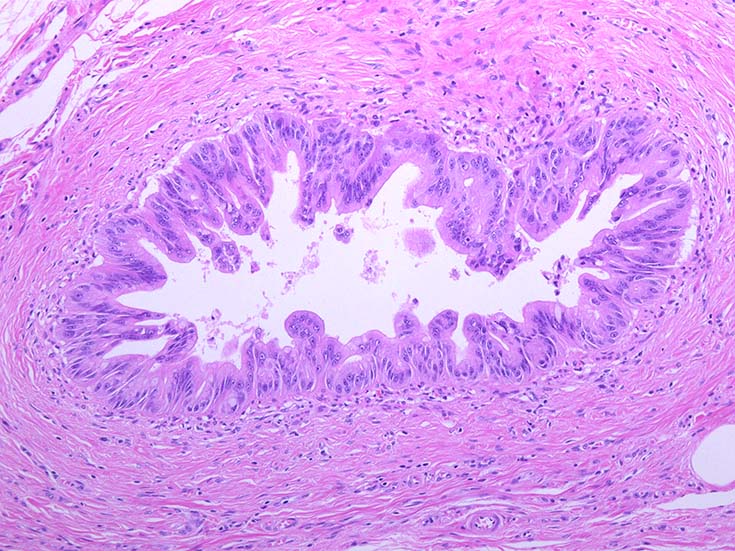

膵上皮内腫瘍性病変 pancreatic intraductal neoplasm(PanIN)*16

Low-grade PanINとhigh-grade PanINの分類

low-grade PanIN

high-grade PanIN

PanINの図譜はJohns Hopkins The Sol Goldman Pancreatic Cancer Research CenterのHome page*19から引用.